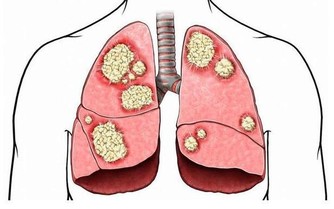

3、損傷腎臟

夏季是痛風“高發期”! 做對5件事,痛風遠離你!

痛風患者體內的尿酸比較高,大量的尿酸鹽在腎臟內沉積,最終導致腎病變。據WHO統計,1/4的痛風患者會出現腎功能衰竭,發展為嚴重的尿毒症。